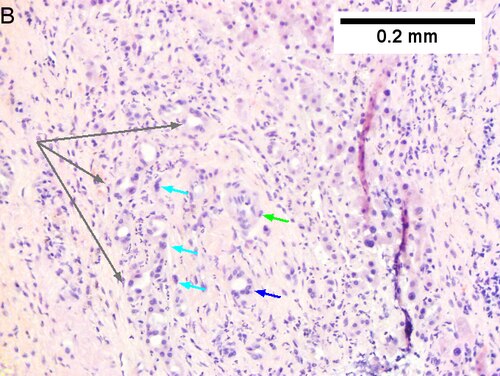

Cholangiocarcinoma, intrahepatic, large duct type. Extremely unfortunate case arising in a pre-teenage girl. A. MRI showing multiple hepatic masses. B. A mass comprising often large ducts abuts uninvolved liver. C. CK7 immunostain emphasizes large, often adjoining ducts. D. Trichrome stain shows spread of tumor into scar with collagen deposition. E. Reticulin stain emphasizes disorderly vertical and horizontal spread of bizarrely shaped acini. F. PAS-D stain shows luminal mucin; note absence of red lining of outside of ducts seen in normal bile ducts/proliferating bile ductules. G. Loss of polarity (varied orientation with respect to base of epithelium) and variable size and shape of nuclei are obvious (Row 3 Right 400X, high pixel image). | |||

Cholangiocarcinoma, intrahepatic, small duct type. Middle aged man with jaundice. A. Small dark tumorous masses [arrows] irrupt scar. B. Cribriforming (net like pattern) of gland in gland [arrow] without intervening stroma, which can be difficult to discern from reactive bile ducts at times. C. A second focus shows, on the left, glands with disorderly spread, further explored, and in the middle, partly formed glands with necrosis, further explored, both diagnostic. D. Note how some glands go up and down [red arrows] & others go right to left [black arrows] showing disorderly spread. E. Note necrotic cell nuclei [red arrows] and incompletely formed glands [black arrows]. F. Nuclear anaplasia is also able to be used for a definite diagnosis, but there is considerable nuclear variability in reactive bile duct proliferations, making it less facile than disorderly spread, incomplete glands, and necrotic nuclei.